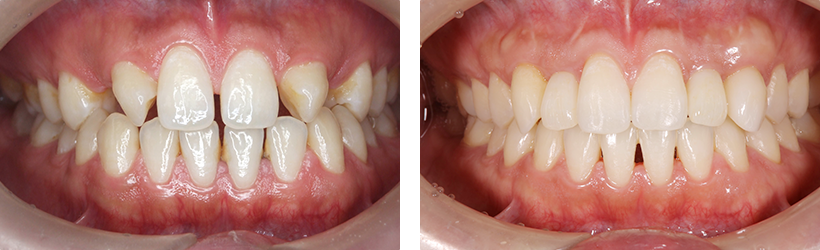

こちらではインプラントと歯周病治療の症例をご紹介いたします。治療のご参考にご覧下さい。

インプラント症例